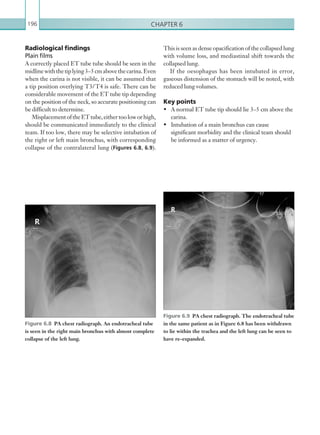

• 190.

Chapter 5168 Haematoma withinthe mediastinum is most often the result of venous bleeding; however, when present thisshouldalwayspromptthesuspicionofaorticinjury. Decelerationinjuriescanalsoresultinbluntinjuryofthe mediastinumagainsttheposteriorsternum,resultingin stranding or haziness of the mediastinal fat (Figure 5.9) or focal haematoma. On CT, mediastinal haematoma appears as dense soft tissue material. Knowledge of the normal morphology of the thymus gland, which is present in children (and some young adults), is vital since this can be falsely interpreted as haematoma. Pneumomediastinum is not uncommon and is best appreciated on lung window settings. Causes include alveolar rupture, extension from pneumothoraces or surgical emphysema, tracheobronchial injury and penetrating trauma. Oesophageal rupture is another important cause, and can be the result of penetrating trauma. Cardiac injury Cardiac injuries can be fatal and should be identified and acted upon as a matter of urgency. CT may demonstrate haemopericardium, although this can also be seen in cases of dissection and myocardial infarction (Figure 5.10). As with a pleural effusion, increased Radiological findings Specific pathologies are discussed separately. In general, as with any polytrauma imaging, an initial survey of CT imaging should be performed in order to quickly identify life-threatening injuries. In the thorax, this includes traumatic aortic injury, tension pneumothoraces and haemopericardium with cardiac tamponade. Once these injuries have been excluded, a more detailed imaging survey can be carried out. In all cases, chest CT imaging should always be inspected on lung window (width 1,600, level 550), soft tissue/ mediastinal window (width 450, level 70) and bone window (width 2,000, level 250) settings in order to appreciate the full spectrum of injury. Mediastinal injury Injurytothemediastinalcontentscanhavecatastrophic consequences, particularly when the aorta and great vessels are involved. It is advisable to assess for major mediastinal vascular injury initially, since injuries to the thoracic aorta can be immediately life threatening. The spectrum of traumatic aortic injury also includes aortic dissection, which should be inspected for (see Chapter 1: Acute aortic syndrome and Thoracic aortic injury). Figure 5.9  Axial image: IV contrast enhanced CT scan of the thorax in the arterial phase. Ill-defined, hazy linear densities can be seen in the medastinal fat anterior to the aortic arch as a result of mediastinal contusional injury (arrow). No active haemorrhage is seen. Figure 5.10  Axial image: IV contrast enhanced CT scan of the thorax in the arterial phase. There is large volume, homogenous fluid within the pericardium surrounding the heart, which in the context of trauma is likely to represent haemopericardium. K22247_C005.indd 168 16/05/15 3:11 AM

• 191.

Trauma imaging 169 duringrespiration. In a pneumothorax, gas within the pleural space causes the lung to separate from the chest wall and collapse. This in itself may reduce respiratory capacity and compromise function. Gas may collect within the pleural space by several means. The most common cause is air leakage from traumatic alveolar rupture. Other causes include blunt and penetrating chest wall injury. On CT, a pneumothorax is seen as a collection of gas surrounding the lung within the pleural space (Figure 5.11). Other features include an absence of vascular lung markings that reach the chest wall and a well-defined lung edge seen within the thorax away from the chest wall. Findings on chest plain film imaging are similar, with a lung edge visible and an absence of vascular markings at the lung periphery in an erect/semi-erect patient (Figure 5.12). In supine patients, however, findings may be more subtle. In this density of pericardial fluid suggests haemorrhage, and the Hu of any pericardial fluid should always be sampled.Thenormalpericardiumshouldbepencilthin and not contain any significant volume of fluid, with a normal fat plane seen between the cardiac chambers and the pericardium. Simple pericardial effusions are not uncommon, and can be seen in pre-existing heart disease. Large pericardial effusions can result in cardiac tamponade, whereby the excess fluid around the heart impairs cardiac function, resulting in impaired venous return to the heart. Pneumothorax A pneumothorax is the result of gas collecting within the pleural space. In normal individuals, the pleural space is a potential space between the visceral and parietal pleura. It normally contains a small volume of fluid to lubricate the pleura and allow movement Figure 5.11  Axial image: IV contrast enhanced CT scan of the thorax in the arterial phase. Viewed on lung window settings, gas is illustrated as areas of low attenuation. There are bilateral pneumothoraces. In addition, there is marked pneumomediastinum and surgical emphysema, which can be seen tracking within and around the muscles of the chest wall. Figure 5.12  AP portable chest radiograph. A large right pneumothorax is demonstrated, with no vascular markings visible. The collapsed right lung is seen as a soft tissue mass adjacent to the right heart. There is no mediastinal shift to suggest tension. K22247_C005.indd 169 16/05/15 3:11 AM

• 192.

Chapter 5170 defect inthe pleura (e.g. broken rib) and through the fascial planes into the subcutaneous tissues. It may also occurasaresultofdirectpenetratinginjurytothechest, resultinginatractbetweenthesubcutaneoustissuesand the outside. On imaging, this is seen as gas overlying the chest within the subcutaneous tissues. This is often a fairly self-limiting condition with treatment aimed at the underlying pneumothorax. However, it may occasionally progress and become extensive resulting in airway compromise. Haemothorax Haemothorax is defined as the presence of blood within the pleural space. The underlying cause may be any cause of haemorrhage within the thorax, such as pleural injury, rib fracture or lung injury. On CT imaging, haemothoraces appear as fluid within the pleural spaces, which is usually denser than simple pleural effusions (Figure 5.14). It should be noted position, gas collects in the most dependent position (anteroinferiorly against the diaphragm), appearing as a deep sulcus sign (Figure 5.13). The main complication of a pneumothorax is the development of a tension pneumothorax. This occurs when gas is able to collect within the pleural space but is not able to escape. This results in a large volume of gas within the pleural space, which exerts considerable masseffect,resulting in shifting of mediastinalcontents to the contralateral side. The mass effect of this raises the pressure within the thorax and compromises venous return to the heart, leading to cardiac failure. A tension pneumothorax ideally should not be seen on imaging as it is a clinical diagnosis requiring immediate intervention.However,ifitisseenonimaging,itshould be immediately decompressed. Pneumothoraces in the context of chest trauma may also result in subcutaneous emphysema. This occurs when gas within the pleural space tracks through a Figure 5.14  Axial image: IV contrast enhanced CT scan of the thorax in the arterial phase. Dependent fluid can be seen in the right pleural space. A right pneumothorax is also seen, and this is therefore a pneumohaemothorax. Figure 5.13  AP chest radiograph. There is a left pneumothorax. In the supine position, gas within the pleural space collects within the most superior part of the thorax, which is the costophrenic recess antero- inferiorly (arrow). K22247_C005.indd 170 16/05/15 3:11 AM

• 193.

Trauma imaging 171 painfulfor the patient, and so can result in splinted breathing and inadequate ventilation, which can lead to atelectasis and infection. They are therefore important to identify in order to prevent complications. A flail segment is defined as two or more contiguous ribs that are fractured in at least two places. The result is a separated segment of the chest wall, which moves independently and paradoxically to the rest of the thoraciccage(Figures5.15,5.16)duringinspirationand expiration. Flail segments may be difficult to manage due to inadequate respiration and pain, and patients may require sedation. Furthermore, patients with flail chest may often have underlying lung contusions, which can further impair respiratory function. that a small amount of blood within simple pleural fluid can be difficult to appreciate visually, and the Hu of pleural fluid should be sampled in the context of trauma (a value 40 Hu is suggestive of haemorrhage). The chest wall and mediastinum should be scrutinised for causes of haemorrhage and for any signs of active contrast extravasation. Rib fracture and flail chest Rib fractures are very common in patients with chest trauma. Isolated, non-displaced fractures may result in a small amount of local lung contusion or small haemothoraces, but otherwise they do not cause a large amount of direct damage. However, they can be very Figure 5.15  Coronal image: IV contrast enhanced CT scan of the thorax and abdomen in the arterial phase. Viewed on bone window settings, a left-sided flail segment is seen with multiple posterior rib fractures (arrow). Right lung contusions are also shown. Figure 5.16  3-D rendered image of the left posterolateral thoracic cage. There are multiple fractures visible along contiguous ribs consistent with a flail segment. K22247_C005.indd 171 16/05/15 3:11 AM